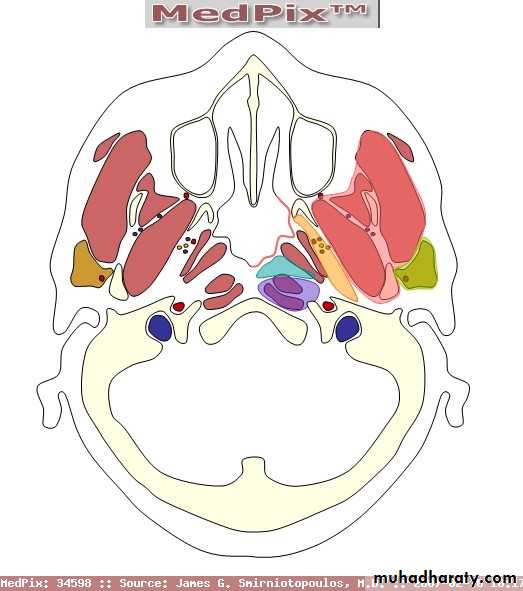

This potential space lies lateral to the pharynx and connects posteriorly with the retropharyngeal space.

It extends from the base of the skull to the hyoid bone.

It's bounded medially by the superior constrictor muscle.

Laterally lies the medial pterygoid muscle, the mandible and the parotid gland.

It's posterior wall is the prevertebral muscles and fascia.

Parapharyngeal Space

Contents

1. Deep cervical lymphnodes.2. The last 4 cranial nerves and the cervical sympathetic trunk.

3. Great vessels of the neck: carotid and internal jugular vein.